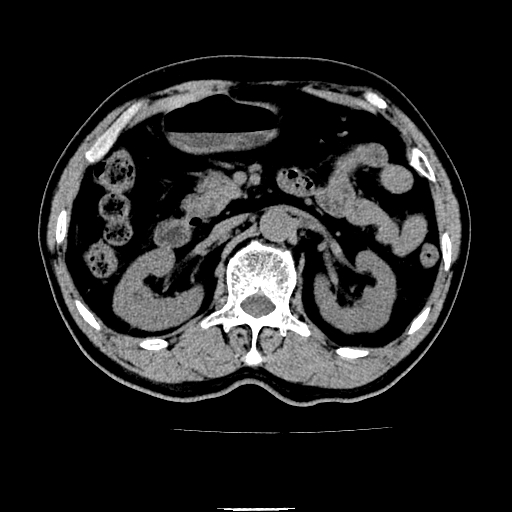

以下是引用chenqiong在2010-3-25 20:56:00的发言:[br]1、胆囊炎,胆囊息肉[br]2、肝内胆管及胆总管扩张,胆总管下端结石[br]3、十二指肠乳头旁憩室

以下是引用zxl51642在2010-3-26 10:47:00的发言:[br]胆囊炎,胆囊息肉,胆总管扩张,但未看到明显肿块,肝内胆管扩张不像恶性,炎性狭窄或阴性结石可能吧,建议mrcp,右肾小囊肿